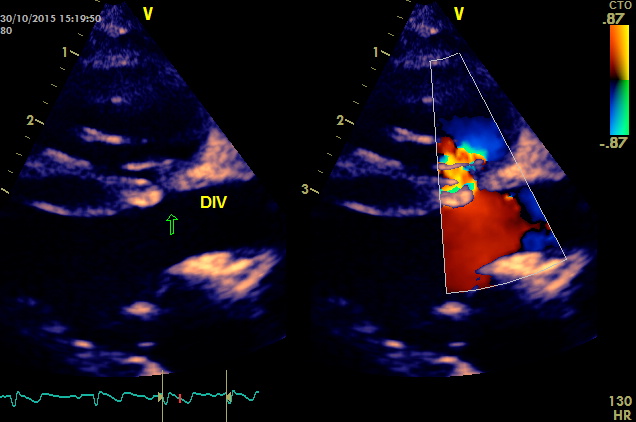

Questo e’ un caso classico che coinvolge la porzione perimembranosa ,la gravita’ del difetto e’ ovviamente proporzionale alla sua ampiezza ,in questo caso il difetto non supera i due millimetri i gradienti tra ventricolo sx e destro sono stimati dal doppler nella norma ,emodinamicamente non dovrebbe comportare lo sviluppo di sovraccarichi significativi del cuore sx . Diversamente i difetti piu’ ampi generano inevitabilmente overcirculation (per lo shunt sx destro emodidamicamente significativo) e sviluppo di scompenso cardiaco sx ,in alcuni casi oltre i due anni l’arteriopatia progressiva generata dall’overcirculation puo’ innalzare la pressione in polmonare e invertire lo shunt.

La diagnosi e’ stata eseguita solo a tre mesi ,la letteratura riporta rari casi di chiusura spontanea il soggetto ( buldog francese femmina di tre mesi) viene regolarmente monitorizzato.

gradiente transventricolare di 178 mmHg questo e’ un pattern restrittivo compatibile con basse pressioni nel cuore di destra da considerare un bene per il soggetto ,gradienti minori indicano innalzamento delle pressioni nel ventricolo destro .

nessuna evidenza di ingrandimento ventricolare